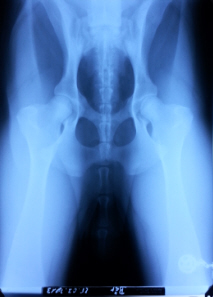

Hüfte, Ellbogen geröntgt, keine Auffälligkeiten